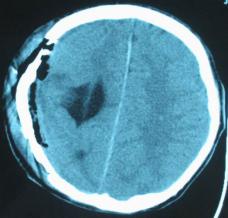

头颅CT和MRI可见颅骨缺损区下方软脑膜囊肿、脑软化灶或脑室穿通畸形(图2)。

图2:①和②CT及骨窗相显示右顶部颅骨缺损,其下方脑组织呈低密度改变;③-⑥MRI右顶局部颅骨缺如,脑组织轻度向外膨隆,右顶叶侧脑室体部旁局部脑组织缺如,代之以囊性长T1、长T2信号。

结果及随访:术后一周复查头颅CT显示脑室穿通畸形明显缩小(图6)。随访3年,未出现癫痫发作。得到很好的治疗,回归社会,正常生活学习工作。

图6:术后一周复查头颅CT显示脑室穿通畸形明显缩小